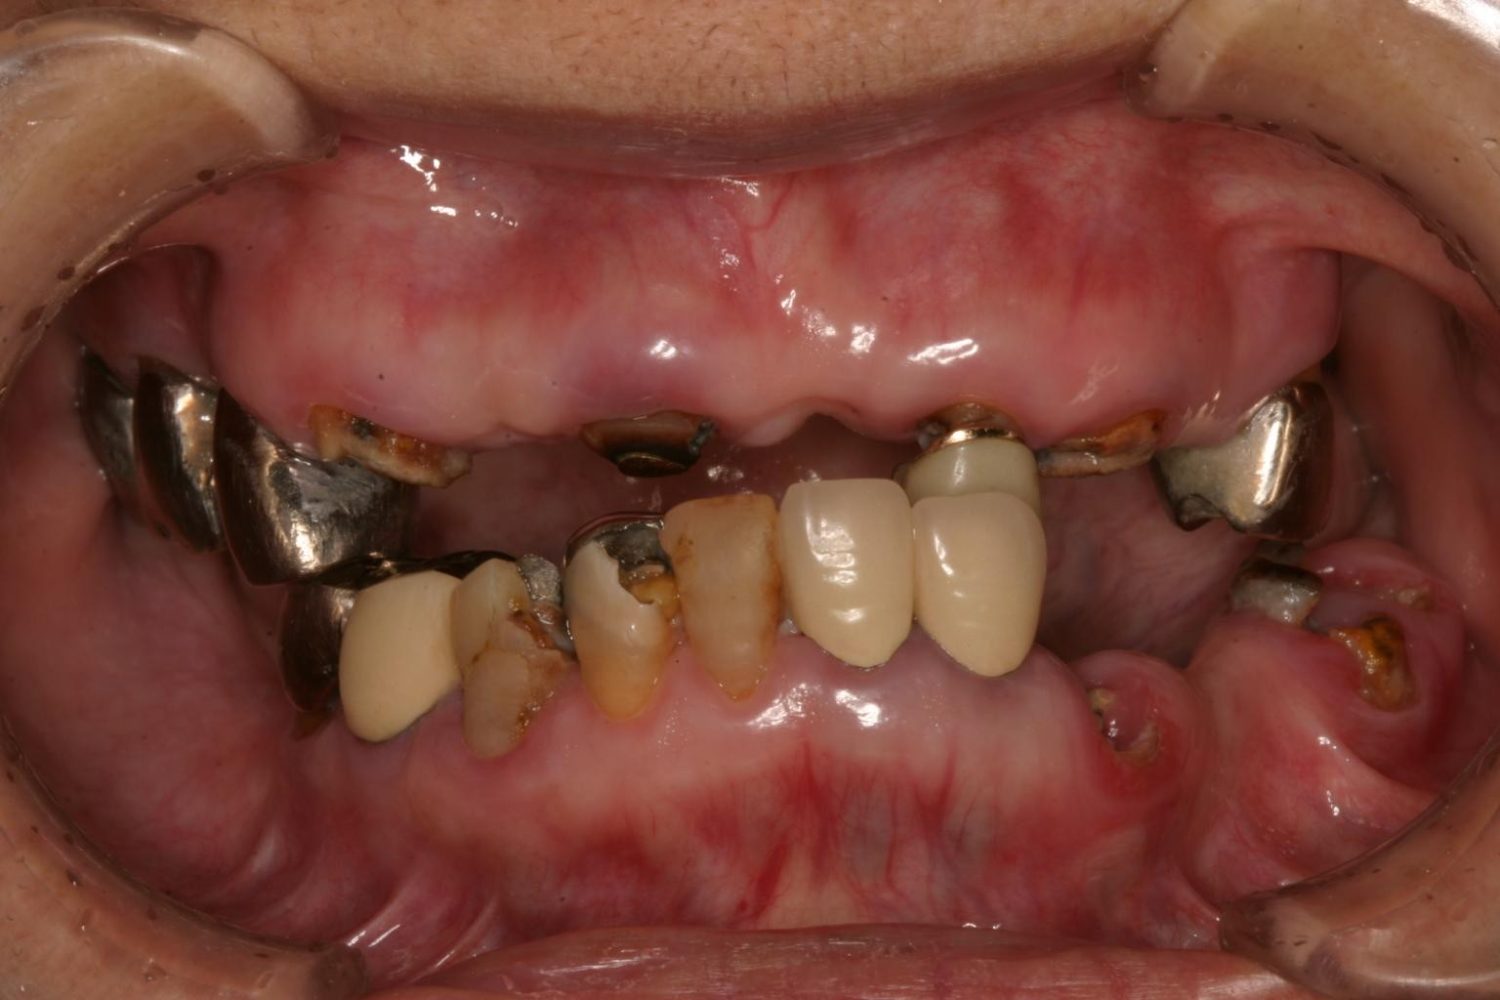

インプラント治療の症例紹介③

Before

After

主訴

むし歯の治療

治療内容

保存不可能な歯の抜歯

下顎にインプラント埋入し咬合再構成

治療費

2,688,400円(税込)

治療期間

14か月

治療回数

21回

想定されたリスク

※上部構造の形態が複雑になるため清掃が難しくなる。インプラント周囲炎の恐れがありました。

多数歯う蝕および多数歯欠損による咬合崩壊、保存不可能な歯の抜歯により上下無歯顎に。下顎に6本インプラント埋入する事で咬合再構成を行った。